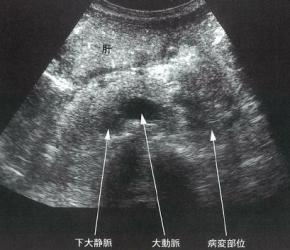

・腹部エコー:ある程度大きくなった癌は斑状の腫瘤として低エコーで

描出されます。また、腫瘍が膵管を圧迫することで

それよりも末梢の膵管が拡張してみえることがあります。